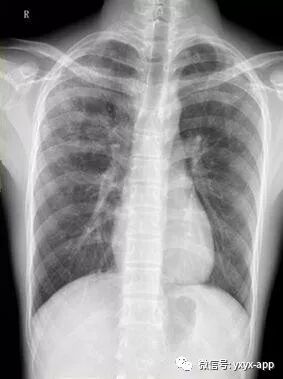

【主诉】体检胸片发现肺部阴影半月余,

【现病史】半月前体检发现肺部阴影,行CT检查,抗炎后复查,无明显吸收、好转

评论:两肺斑片状磨玻璃影,与周围组织分界清楚,呈“地图样”表现,部分病变延伸至胸膜下,部分小叶间隔增厚,气管居中,肺门及纵膈未见肿大淋巴结影,未见胸腔积液。患者青年男性,临床症状轻微影像表现严重,抗炎治疗无效。考虑肺泡蛋白沉积症

【结果】肺泡灌洗病理证实:肺泡蛋白沉积症